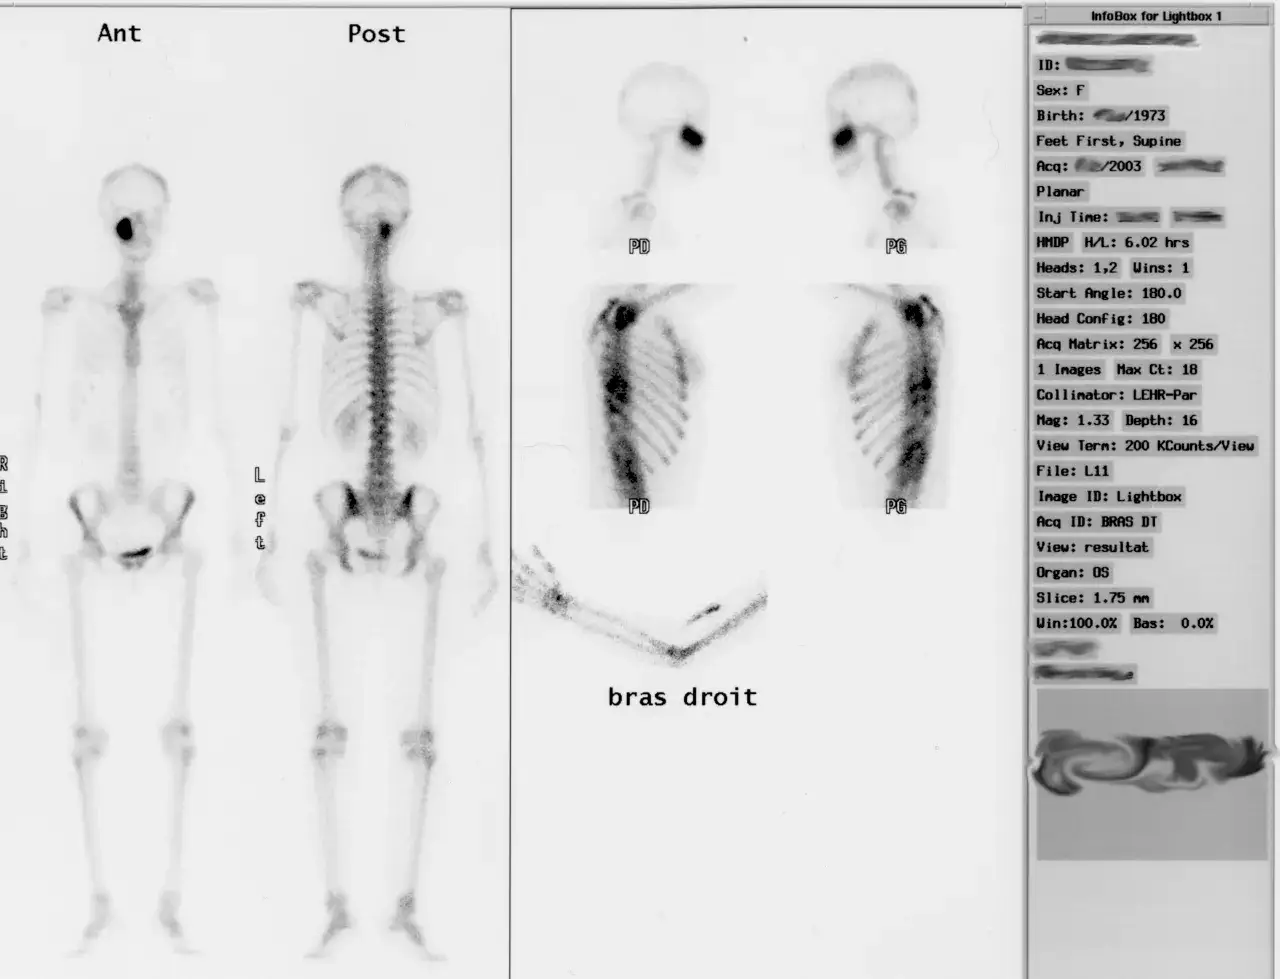

Po podaniu radioznacznika, specjalna aparatura zwana gammkamerą, rejestruje emitowane przez niego promieniowanie. Na podstawie tych danych tworzony jest obraz całego szkieletu, czyli tak zwany scyntygram. Dzięki temu możemy "zobaczyć" zmiany w kościach, często jeszcze zanim dadzą one o sobie znać w inny sposób, co jest kluczowe dla wczesnej diagnostyki i skutecznego leczenia. To właśnie ta zdolność do wczesnego wykrywania sprawia, że scyntygrafia jest tak cenionym narzędziem.

Najczęściej wykonywana jest scyntygrafia statyczna. To standardowe obrazowanie całego szkieletu, które pozwala na ogólną ocenę aktywności metabolicznej kości. Jest to badanie, o którym najczęściej myślimy, mówiąc o scyntygrafii kości.

Etap 3: Skanowanie gamma-kamerą ile to potrwa i czy naprawdę trzeba leżeć bez ruchu?

Kiedy okres oczekiwania dobiegnie końca, zostaniesz zaproszony do pomieszczenia z gammkamerą. Bezpośrednio przed skanowaniem personel poprosi Cię o ponowne opróżnienie pęcherza. Następnie położysz się na specjalnym stole, który jest częścią gammkamery. Sama gammkamera będzie powoli przesuwać się nad Twoim ciałem, rejestrując promieniowanie emitowane przez radioznacznik. Skanowanie trwa zazwyczaj od 15 do 60 minut, w zależności od zakresu badania i używanego sprzętu.